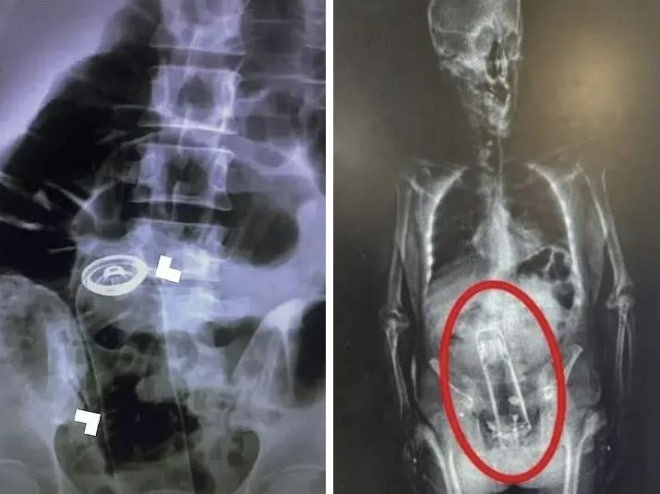

“항문에 왜 이런 게” 안경·문손잡이·보온병까지…美 응급실 공개 목록 ‘충격’